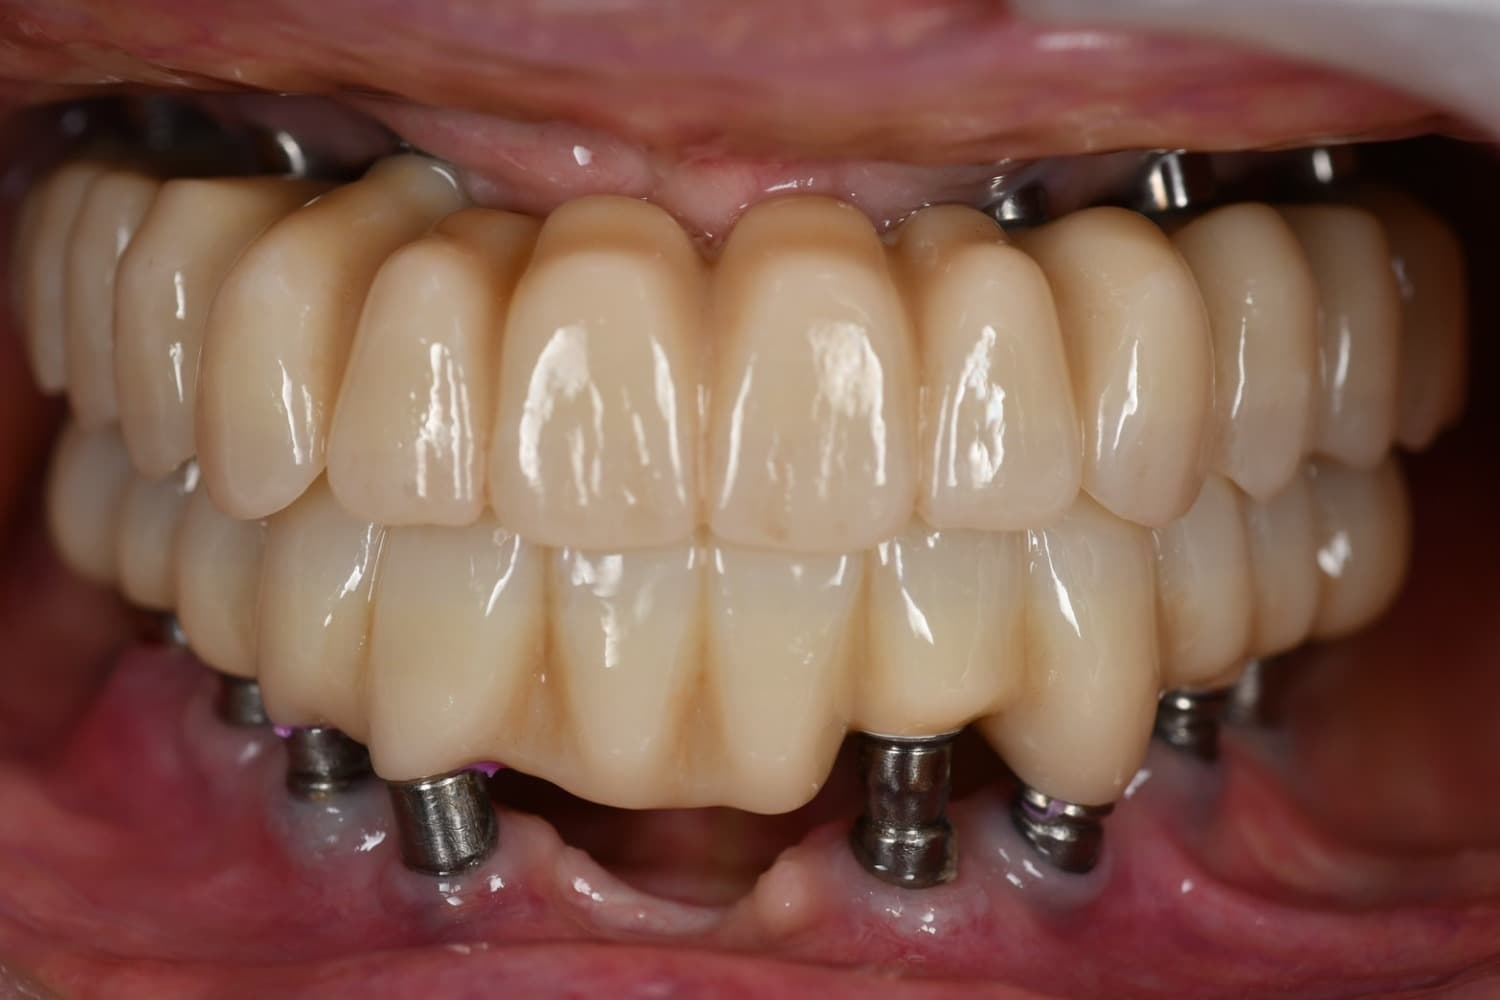

上顎の全顎の即時インプラント(40代女性)

After

上顎の全顎の即時インプラント(1Dayトリートメント) 仮歯まで1日で入ります。 ※治療後も定期的なメンテナンスは必要